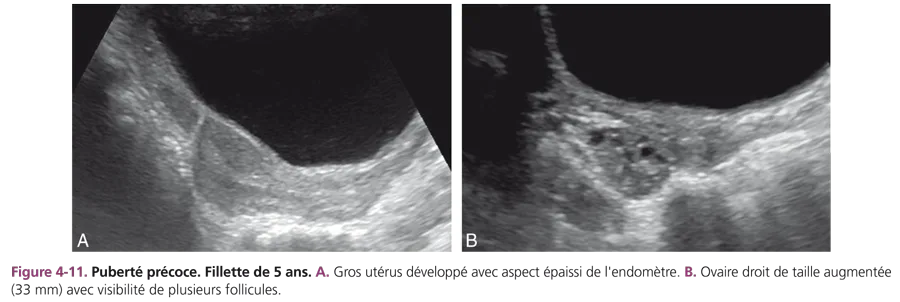

Puberté précoce centrale Elle touche 9 filles pour 1 garçon et est très souvent idiopathique (plus de 90 % des cas). Elle est suspectée cliniquement devant un développement harmonieux des caractères sexuels secondaires, une accélération de la vitesse de croissance et une avance de l’âge osseux. L’échographie pelvienne montre un développement utéro-ovarien plus ou moins évolué (fig. 4-11). Des kystes folliculaires d’hyperstimulation peuvent être visualisés dont l’échographie contrôle le caractère rapidement régressif.